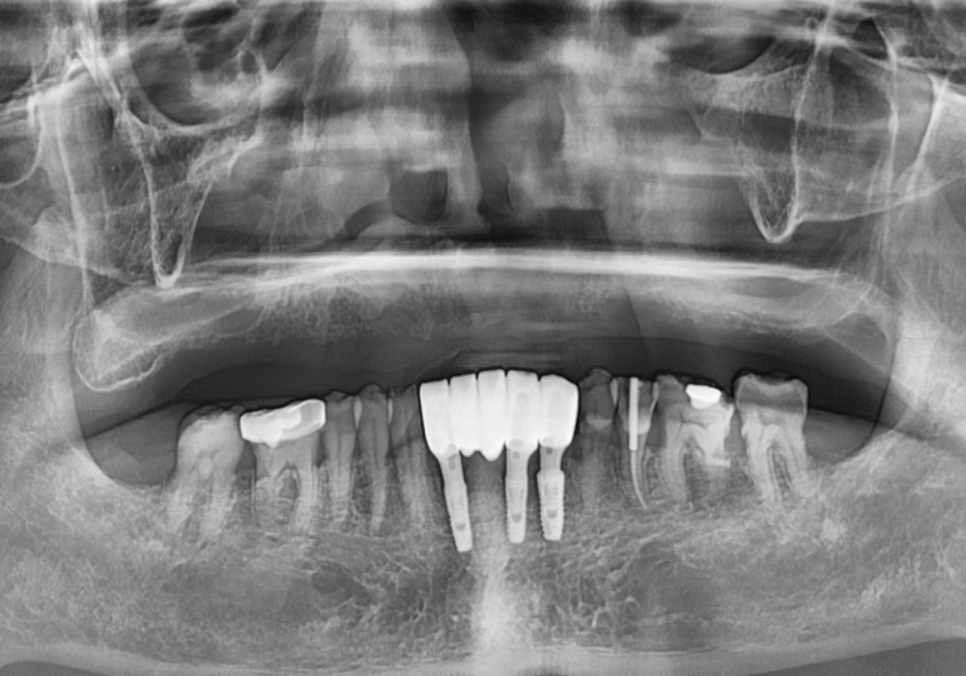

방사선 사진을 보니

잇몸뼈가 전체적으로 아주 얇아져 있었죠.

위턱 임플란트가 어려운 이유는 두 가지입니다.

아래턱이 단단한 나무 같다면,

위턱은 상대적으로 무르고 밀도가 낮습니다.

그만큼 임플란트를 단단하게 고정하기가 어렵죠.

위턱 뒤쪽에는 코와 연결된

뻥 뚫린 공간인

'상악동'이 있습니다.

치아가 오래 없었던 분들은

뼈가 점점 얇아져

정작 임플란트를 심을 뼈는

2~3mm조차 남지 않은 경우가 많습니다.

이때 필요한 것이

바로 '상악동 거상술'입니다.